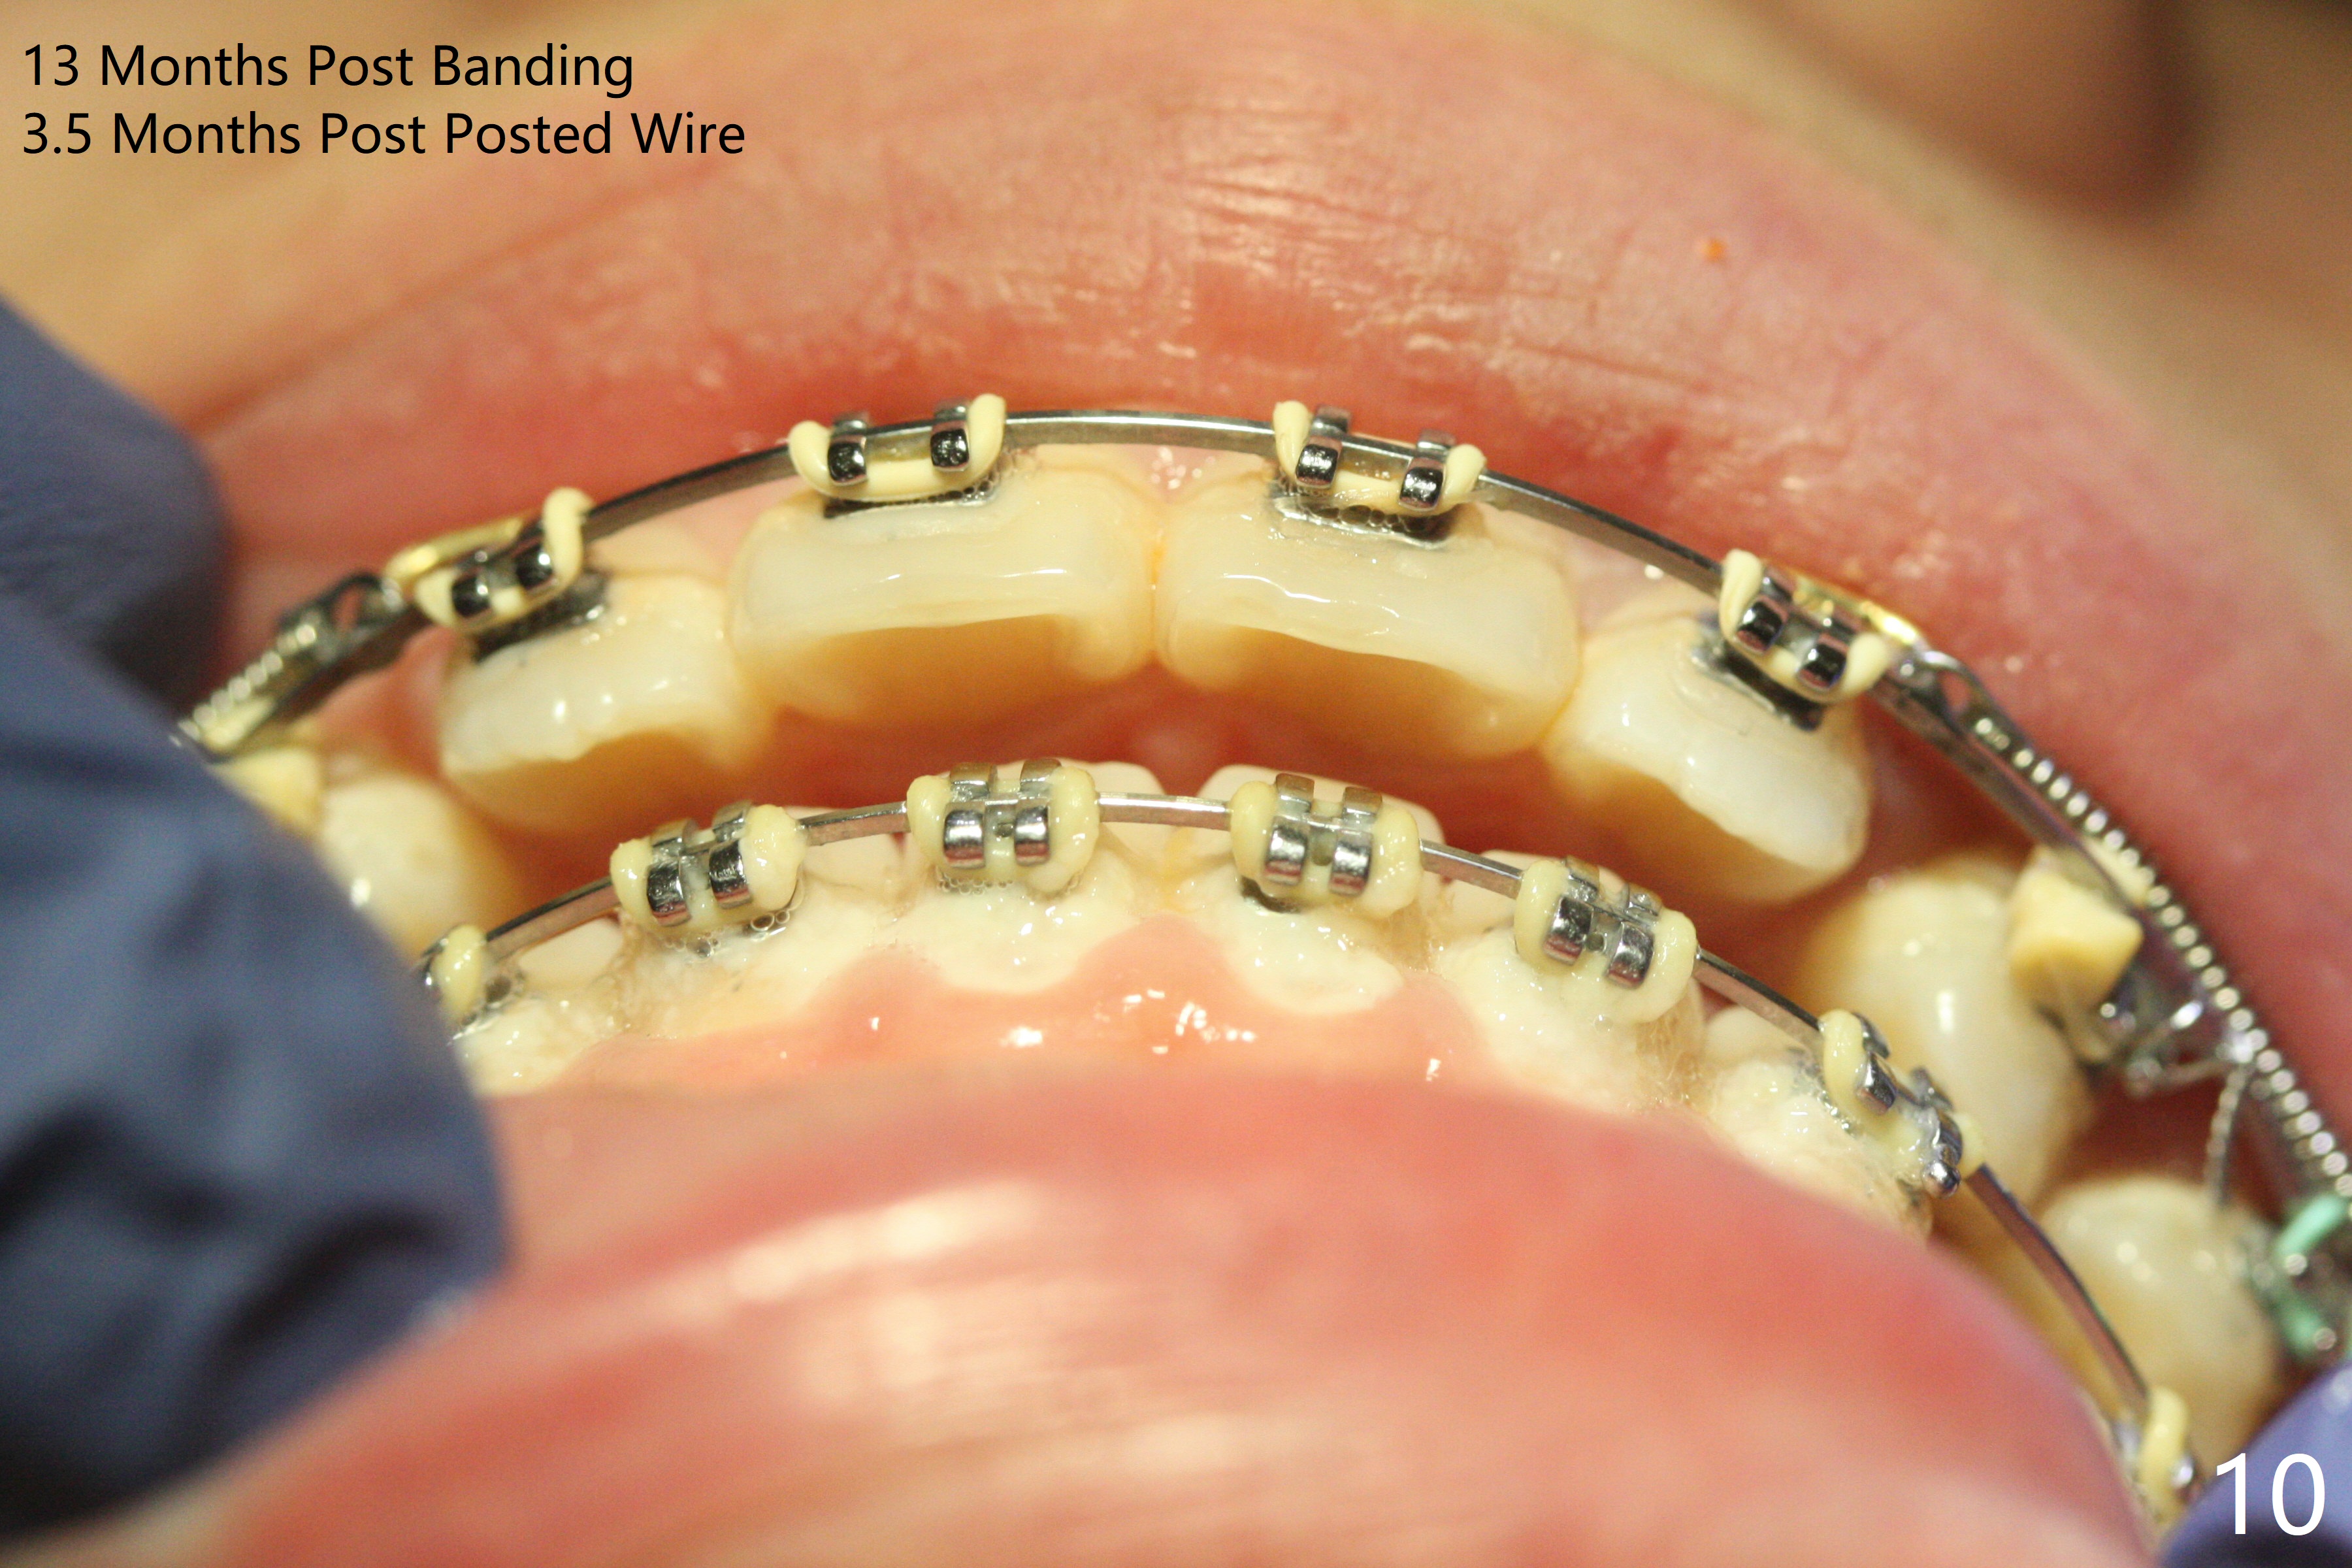

Two weeks post extraction of 4 bicuspids, brackets and bands are placed in 20 teeth (Fig.1-3, 14 niti). No bands are placed at 7s because of short crowns and tight contacts. When 16x16 wires are used, start Class II retraction. The latter is initiated with elastics when 18 ss wires are placed (Fig.4,5). U3s have been distalized with closed springs for 3 months (Fig.6,7). U2s are close to distalization 13 months post banding, 3.5 months post posted wire (Fig,8,9) with overjet (Fig.10). Class II retraction is re-initiated. When the upper incisors are retracted, the anterior overjet remains large. It appears that U6s have been retracted anterior, as indicated by the space between U6/7 (Fig.11), because of no use of U7s as anchors. Brackets are just placed with 18 niti arch wire. They will be retracted distal using the rest of the upper teeth and lower teeth (using Class II retraction) as anchor. There is root resorption of the upper anteriors 2 years 1 month post banding (Fig.12,13).